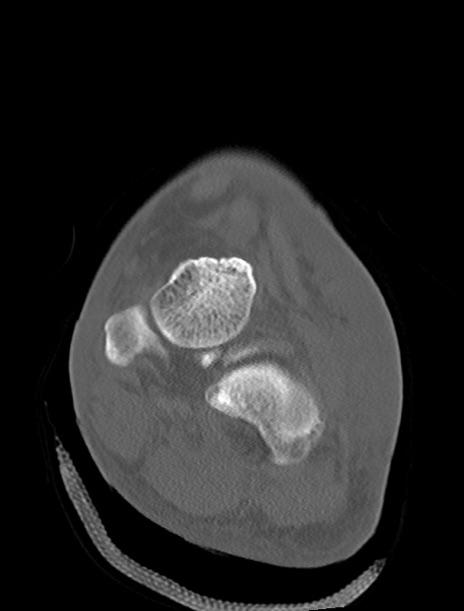

症例37 左足関節CT(冠状断像)

左足関節CT

横断像